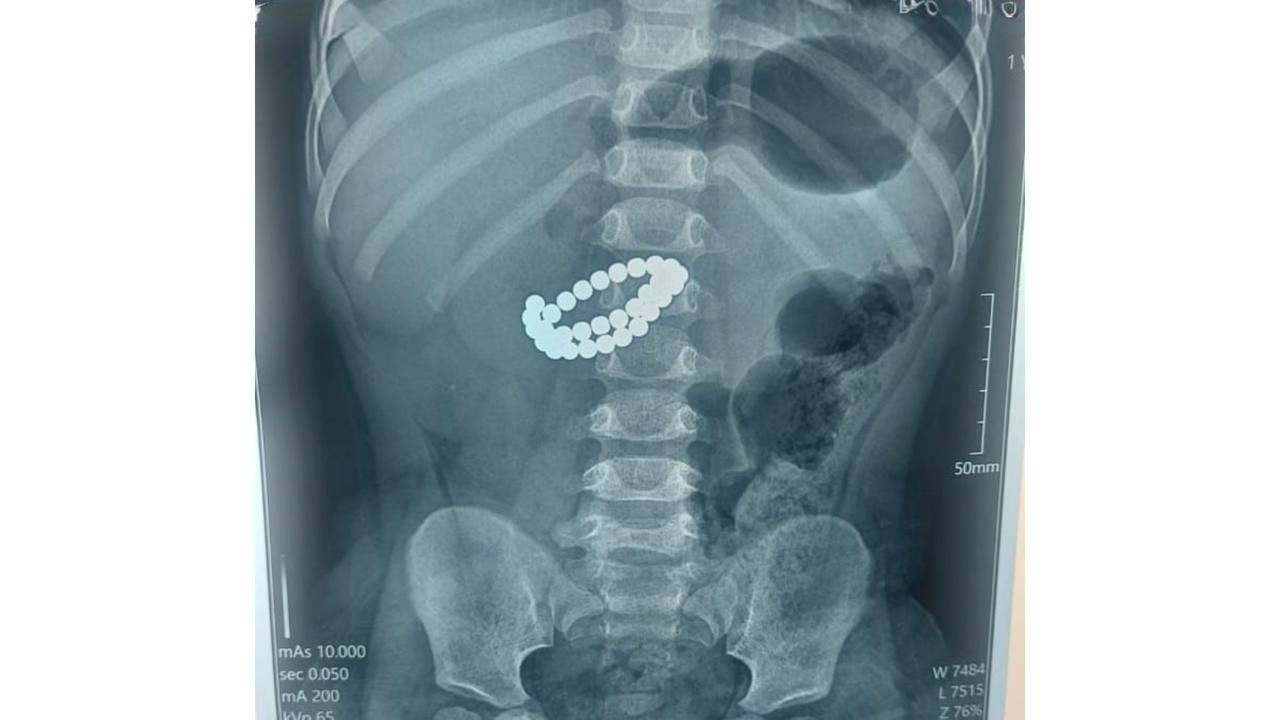

Алматыда 1 жасар сәби 31 магнит жұтқан: «Ішек қабырғасын теседі»

Алматыда дәрігерлер бір жас тоғыз айлық сәбидің ішегінен 31 магнитті алып шығып, оны аман алып қалды, деп хабарлайды Qazaqtoday ақпарат агенттігі.

Аурухананың қабылдау бөліміне өте ауыр халде түскен сәбиге тексеру жүргізгенде, оның ішегінде 31 магнит бары анықталды. Медицина мамандары ащы ішектің көптеген жерден тесілгенін және іріңді перитонит (іш пердесінің қабынуы) диагнозын қойды.

«Магниттің қауіптілігі сол – ағзаға бөлек-бөлек түскен соң, олар ішектің ішінде бір-біріне тартыла бастайды. Салдарынан ішек қабырғалары қысылып, қан айналымы бұзылады, тіндер өле бастайды да, тесіктер пайда болады. Осылайша санаулы сағатта перитонит дамиды», — деп түсіндірді орталықтың хирургі Асқар Ризванов.

Дәрігерлер шұғыл түрде лапаротомия (іш қуысын тіліп ашу) жасап, магниттерді алып тастады. Содан соң ішектегі тесіктерді тігіп, іш қуысын толық тазартты.